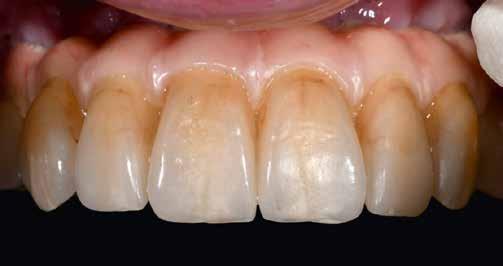

Interdiszciplináris fogászati kezelés myofunkcionális készülék, alignerek és protetikai ellátás alkalmazásával

MED. DENT Abradált frontfogakkal rendelkező felnőtt páciens interdiszciplináris kezelése